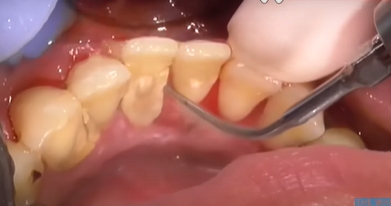

치석은 오랜 시간 쌓이면서 잇몸과 치아 사이를 가리고 있던 돌 같은 물질입니다. 이 치석이 갑자기 떨어지거나 스케일링으로 제거되면 그동안 가려져 있던 치아뿌리나 잇몸 틈이 드러나면서 공간(구멍)이 생긴 것처럼 보일 수 있어요.

특히 아래와 같은 경우라면 구멍이 더 쉽게 생길 수 있습니다:

- 오랫동안 스케일링을 하지 않아 잇몸이 치석에 눌려 있던 경우

- 치주염이 진행되어 잇몸 뼈가 약해진 상태

- 치아 사이 틈이 넓은 구조

- 치석 제거 후 제대로 된 관리가 안 된 경우